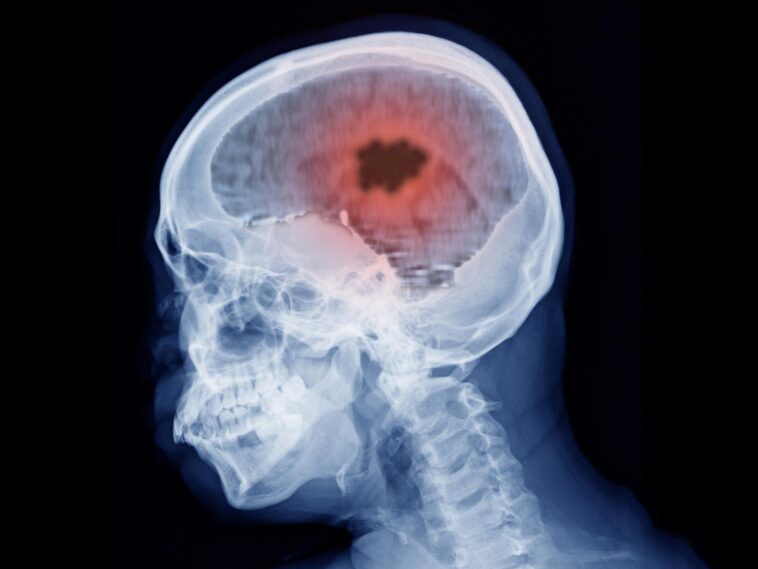

L'utilisation prolongée de certains médicaments à base d'hormones progestatives a été associée à un risque plus élevé de méningiome intracrânien, un type de tumeur cérébrale, selon une étude française publiée récemment dans Le BMJ.

Les méningiomes sont pour la plupart des tumeurs non cancéreuses situées dans les couches de tissus (méninges) qui recouvrent le cerveau et la moelle épinière. Des facteurs tels que l’âge avancé, le sexe féminin et l’exposition à trois progestatifs à forte dose (nomégestrol, chlormadinone et acétate de cyprotérone) sont déjà connus pour augmenter le risque de méningiome.